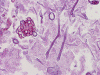

Pathology of the Case: Multiple tissue samples were from several locations of the sinuses were rerceived. The specimen was in the form of small aggregates of irregularly shaped, tan brown, necrotic debri with clotted blood and purulent material. Admixed with the soft tissue were small fragments of bone. Frozen section of “left nasal contents” reveals fungal organisms with hyphae and nonviable collagenous tissue, suspicious for invasive fungal infection. On permanent sections, about 99% of the tissue is composed of necrotic debri. There is an abundance of fungal organisms.  While some of the organisms are scattered, there are areas suggestive of an angioinvasive pattern. These organisms may well be recognized by hematoxylin and eosin stain but also well demonstrated by PAS and GMS stain. The organisms contain pauciseptate, “ribbon-like,” irregular hyphae with acute and right-angle branching. Associated with the hyphae are globus-shaped, pigmented sporangia  and columella (Panel C, D, and E). The hyphae are wide and here show acute angle branching. Occasional septum can be seen (Panel  D and E). The sporangium on the left shows angulated sporangiospores (Panel C and E). These features are characteristic of the class Zygomyycetes, order Mucorales. This order includes the Rhizopus and Mucor species. Fungal culture identified a Rhizopus specie as well as Aspergillus. The pathologic features are most compatible with a sino-nasal mixed fungal infection in an immunocompromised host.

All Zygomycota share similar morphologic features with broad, thin-walled, pauciseptate hyphae. Typically the different genera can be separated by the appearance of their sporangia and sporangiophores grown in culture media. In this case, the globus shape and brown pigmentation of the sporangia along with the angulated shape and striations of the sporangiospores are consistent with the diagnosis of Rhizopus species. In the rare instance that these features are identified on tissue section, a presumptive diagnosis can be made. This diagnosis should be followed up by fungal culture confirmation. Diagnosis and management of fungal infection in immunocompromised patients often requires a multidisciplinary approach. Careful histologic evaluation may provide early identification of mucormycosis and save valuable time in directing focused therapy.